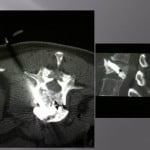

Vertebroplasty techniques in the case of lytic mestastatic lesions or myelomatic with pejorative invasion of the anterior or posterior walls.

The tumoral extension at the posterior wall with or without epidural inflammation constituted a few years ago a counter-indication to vertebroplasty. The experience of conventional radiology teams allowed to progressively reaching that limit. Numerous precautions are necessary to avoid complications.

In case of lytic tumoral lesion invading the anterior wall.

The trocar is positioned on the most posterior part of the tumor so that the filling is performed from back to front and to better control the anterior diffusion. A control scanner confirms the correct position of the trocar at the intra-tumoral level. The injection of the cement is performed at the end of the work, that is during the really thick phase. The filling is performed step by step slowly to fill the lesion completely. The injection of cement is performed under scopic control and verifies the absence of too anterior diffusion at the level of soft pre-vertebral parts. The cement viscosity is key, the risk of vascular leaks, in particular arterial, by neo vascular growing is possible, the cement going against of the blood flow (amoretti). The lateral scopy in this case can be taken into default, the vascular leak being projected at the level of the vertebral body. The cement embolus can also reach an medullar artery depending on the level.

In case of lytic tumoral lesion invading the posterior wall.

The major risk is compression of the spinal roots by the cement. An excellent radio-opacity of the cement is fundamental to perfectly limit its position and its diffusion under continuous scopic control.

We position the trocar at the level of the most anterior portion of the tumor and cross the adjacent bone. We slowly inject a few drops of cement at the level of the vertebrae not invaded, then as the cement is getting more dense, we withdraw while injecting cement.

The lesion must be filled as much as possible. An bilateral entrance way can be very useful for an optimal filling. In case of a pedicular contact, the withdrawal of the trocar is performed slowly while injecting the rest of the very thick cement little by little to create a bone bridge under scopic guidance. The risk to reach nervous root is important by extension in the foramen, a perfect control of the move s compulsory to avoid nervous complications.